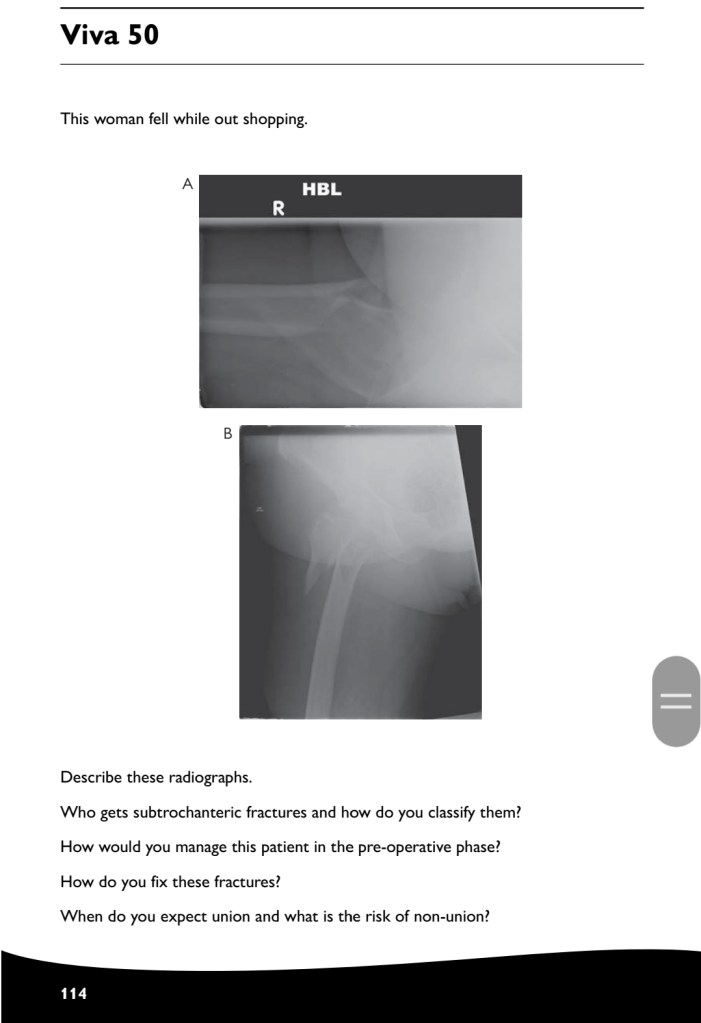

Revision how to answer your case